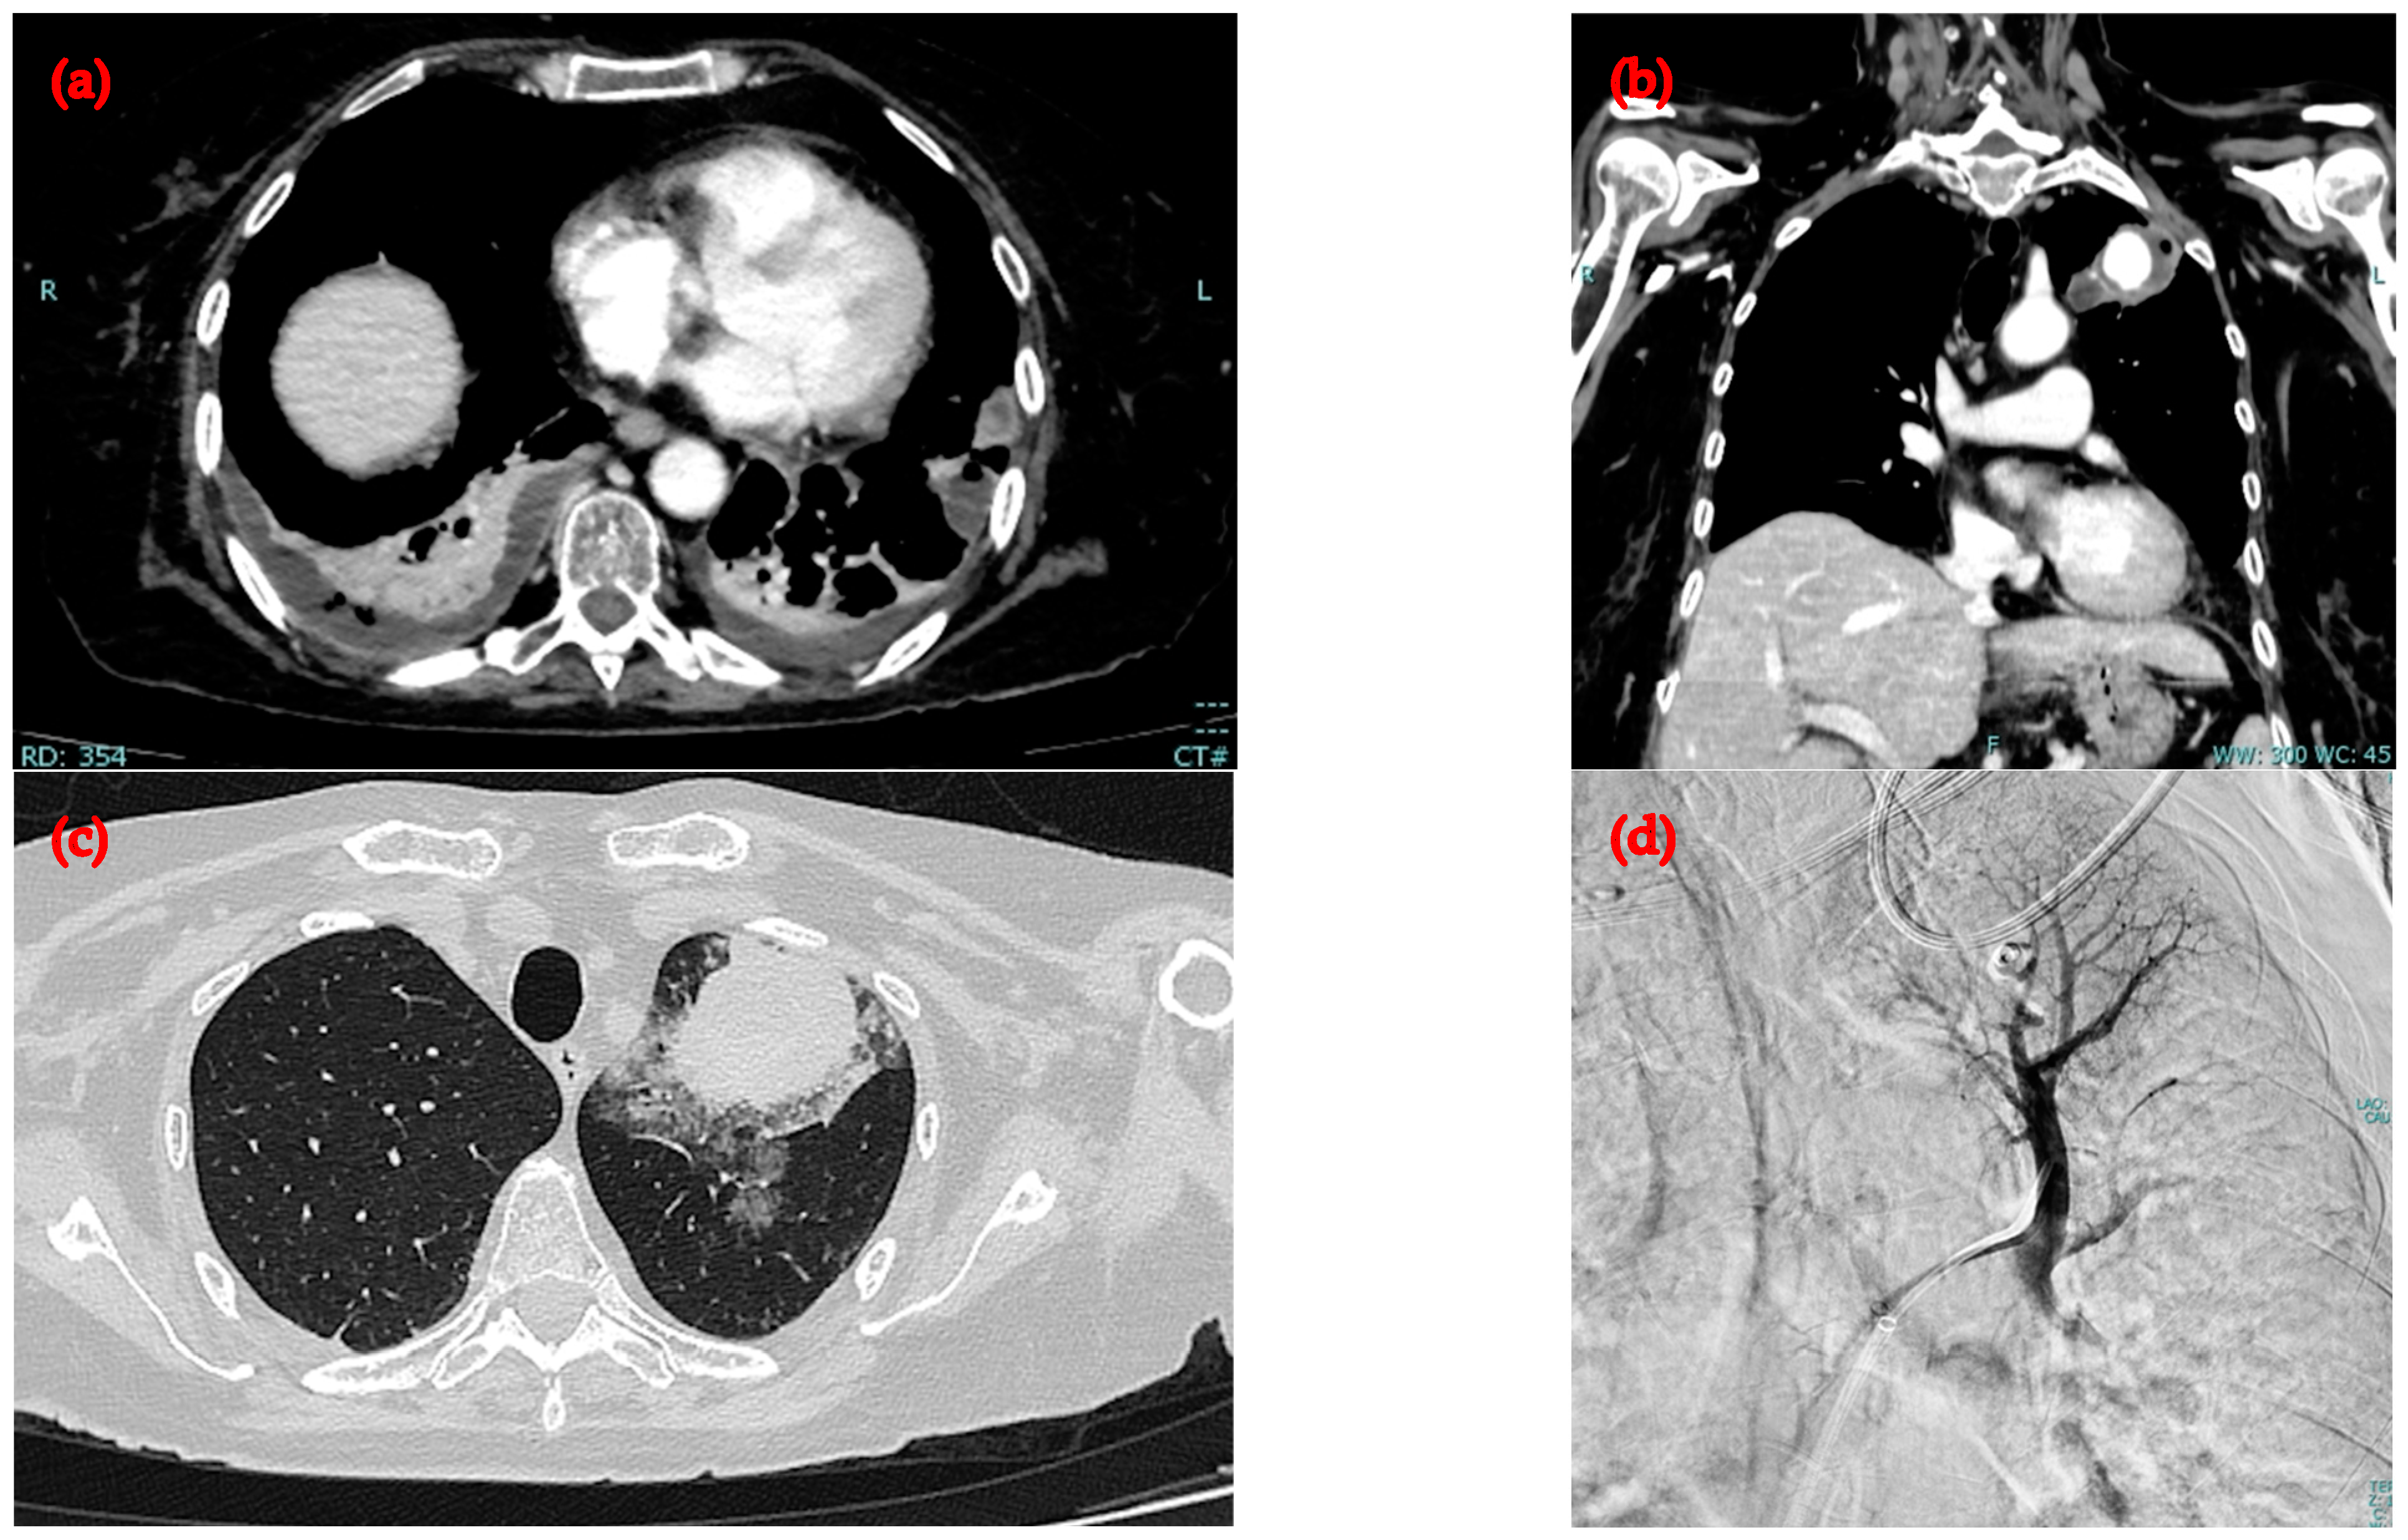

2.1. First Admission to the Hospital

2.2. Second Admission to the Same Hospital